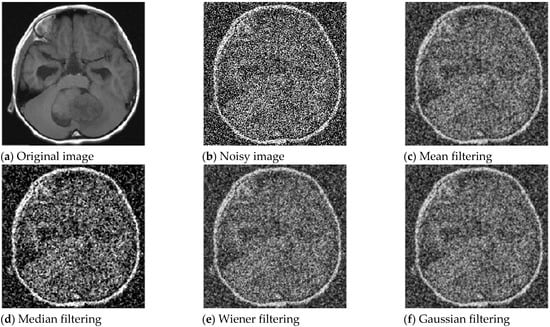

5.3. Magnetic Resonance Imaging Image

An MRI grayscale image with pixel size of was used for testing. The noise is Gaussian white noise with a mean value of 0 and an intensity of 0.3. Figure 8 shows the MRI grayscale image, the MRI noise image, the denoising MRI image by mean method, median method, Wiener method and Gaussian method. The PSNR performance comparison results of the processed MRI images are shown in Table 5. As can be seen from Table 5, compared with the PSNR of noisy MRI images, the PSNR value of MRI images after mean filtering, median filtering, Wiener filtering and Gaussian filtering is small, the PSNR value improvement effect is not obvious, and the image enhancement effect is not good.

Figure 8.

MRI image enhancement for four classical filtering methods.